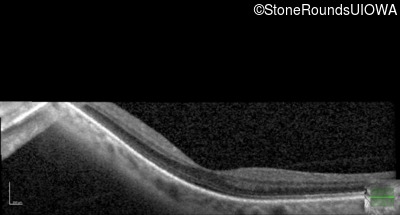

Optical Coherence Tomography - Right - 20/25 -3

Exemplar / OCT Stack